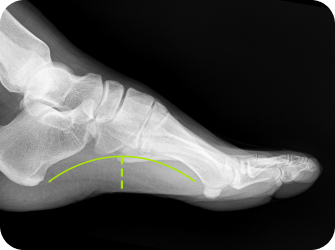

발 모양에 따라

▲ 평발

▲ 요족

▲ 정상발

평발형 오다리

요족형 오다리

평발형 엑스다리

요족형 엑스다리

휜다리는 발과 다리의 교정뿐 만아니라 골반과 척추의 밸런스를 맞춰야하는데 이때 가장 필요한 것이 족부 교정입니다.

발과 발목의 변형을 교정할 필요가 없는 휜다리는 흔치 않으며 발을 교정해야 교정후 재발 걱정이 없습니다.

족부교정

맞춤형 깔창을 통해 평발과 요족 등

발의 변형을 바로 잡아

하지의 회전을 최소화

족궁 높이 측정

발 뒤꿈치 각도 검사